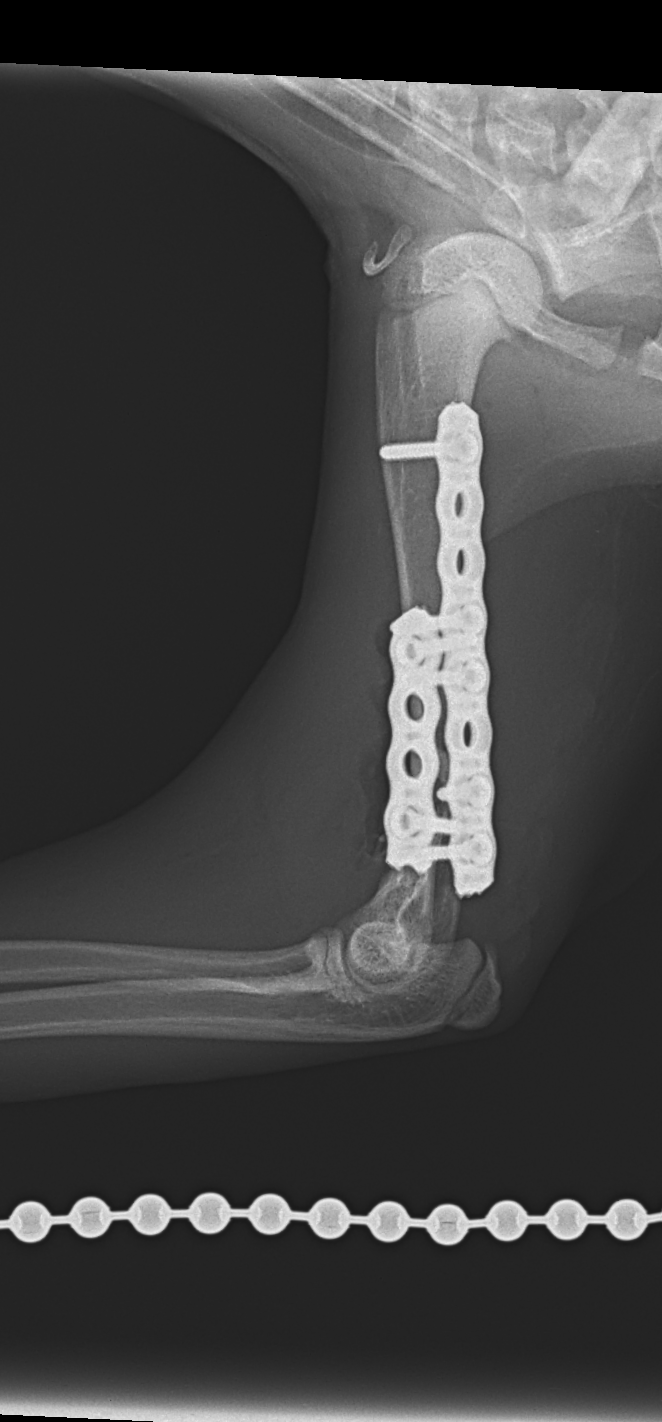

上腕骨遠位粉砕骨折

若い猫ちゃんが部屋で遊んでいたところ、不運にも上腕骨を粉砕骨折してしまったとのこと。かかりつけ医から固定術の依頼がありました。粉砕部分をOrthogonal Plateで固定術を行いました。